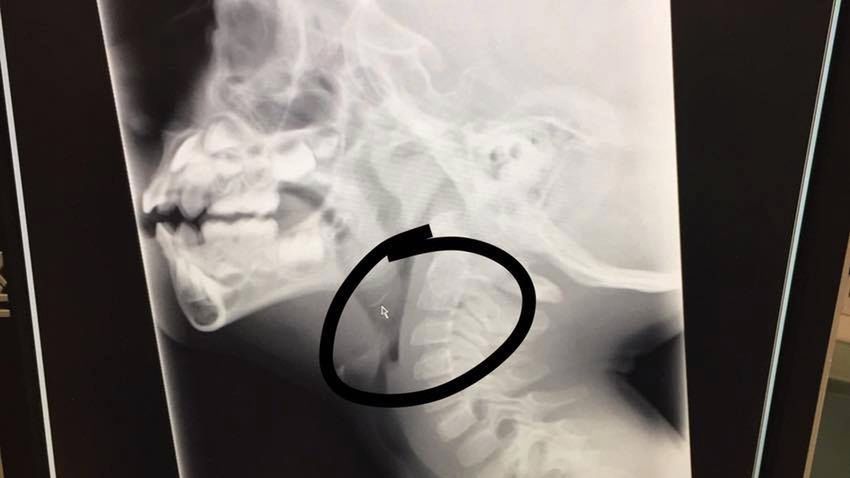

Metalowe elementy szczotki czyszczącej! Okazało się, że kolejne kawałki kurczaka też je miały. Zrobione po dwóch godzinach prześwietlenie mojego synka potwierdziło nasze obawy. Ollie nie mógł przełykać!

Mały Ollie połknął kawałek metalu

Mały Ollie połknął kawałek metalu © Facebook @Jenna Kuchik